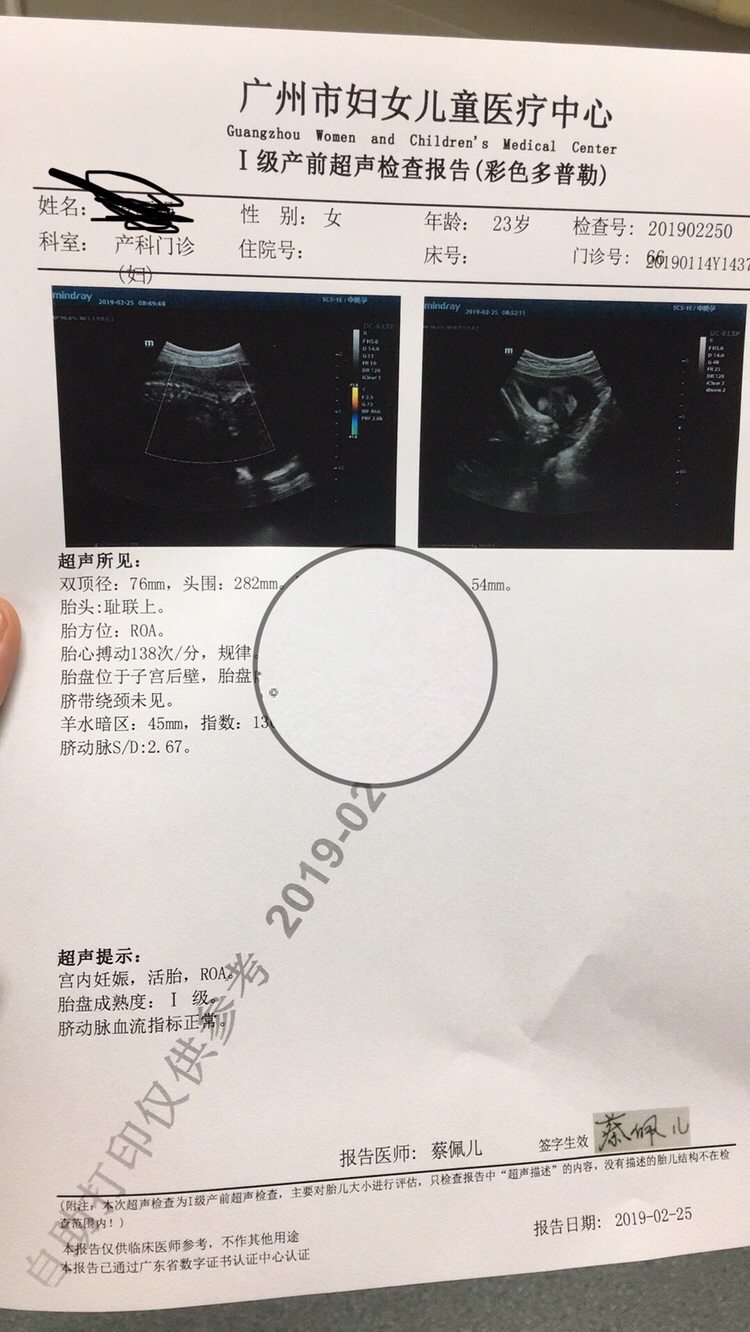

产前检查 前置胎盘